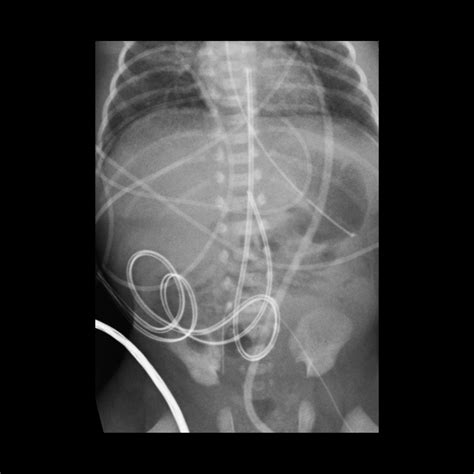

• Malposition: Incorrect placement of the catheter can lead to ineffective therapy or complications such as arrhythmias.

To mitigate these risks, healthcare providers must adhere to strict protocols for insertion, maintenance, and monitoring of the Umbilical Venous Catheter. Regular assessment of the catheter site, prompt removal if signs of infection are detected, and careful monitoring of the infant's vital signs are essential.